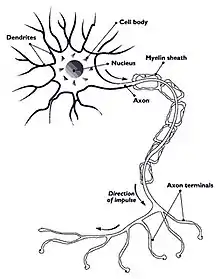

Myelitis is inflammation of the spinal cord which can disrupt the normal responses from the brain to the rest of the body, and from the rest of the body to the brain. Inflammation in the spinal cord can cause the myelin and axon to be damaged resulting in symptoms such as paralysis and sensory loss. Myelitis is classified to several categories depending on the area or the cause of the lesion; however, any inflammatory attack on the spinal cord is often referred to as transverse myelitis.

- Neurotropic growth factors regulate growth, survival, and plasticity of the axon. They benefit nerve regeneration after injury to the nervous system. They are a potent initiator of sensory axon growth and are up-regulated at the lesion site. The continuous delivery of neurotropic growth factor (NGF) would increase the nerve regeneration in the spinal cord. However, the excessive dosing of NGF often leads to undesired plasticity and sprouting of uninjured sensory nerves. Gene therapy would be able to increase the NGF efficacy by the controlled and sustained delivery in a site-specific manner.

The possibility for nerve regeneration after injury to the spinal cord was considered to be limited because of the absence of major neurogenesis. However, Joseph Altman showed that cell division does occur in the brain which allowed potential for stem cell therapy for nerve regeneration.[15][16] The stem cell-based therapies are used in order to replace cells lost and injured due to inflammation, to modulate the immune system, and to enhance regeneration and remyelination of axons.[17] Neural stem cells (NSC) have the potential to integrate with the spinal cord because in the recent past investigations have demonstrated their potential for differentiation into multiple cell types that are crucial to the spinal cord. Studies show that NSCs that were transplanted into a demyelinating spinal cord lesion were found to regenerate oligodendrocytes and Schwann cells, and completely remyelinated axons.[18]